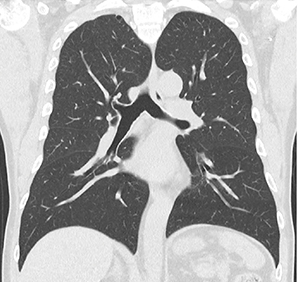

図2 腹部造影3相撮影

a:動脈相

b:門脈相

c:平衡相

AiCE-i適用で高画質画像を提供